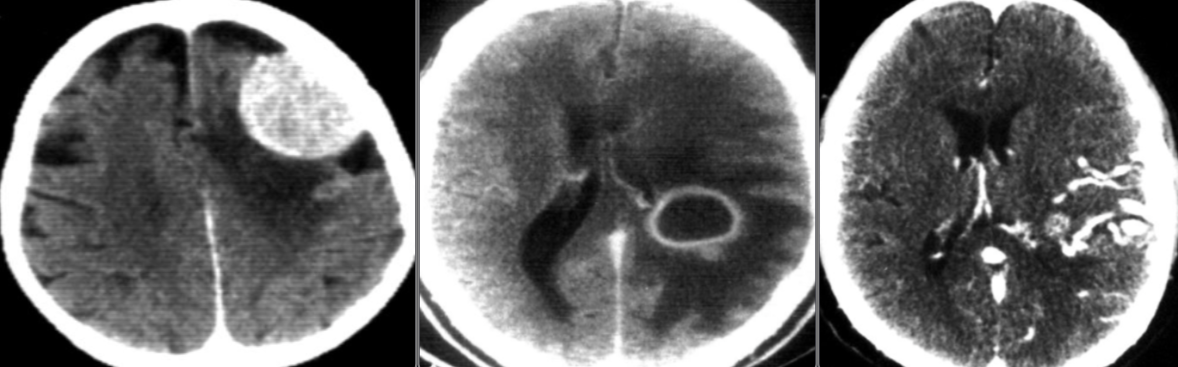

CT Brain IN EMERGENCY

Epidural hematoma

- Convex inner margin (lens-shaped)

- High density area

CT brain - Acute subdural hemorrhage

- crescent shape

CT brain - Chronic subdural hemorrhage

- Concave

CT brain - Acute on chronic subdural hematoma

- Inner margins are concave

A. Imaging study. *CT head *(without contrast; axial plane)

B. What is the most likely diagnosis? Subarachnoid hemorrhage

- Multiple areas of high attenuation in the basal cisterns, Sylvian fissures, and sulci are

- characteristic of extensive subarachnoid hemorrhage.

Intra ventricular hemorrhage

- Anterior/Posterior Horns hemorrhages

Intracerebral hemorrhage

Infarction appear hypodense on CT without contrast

Sign? Hyperdense sign in stroke; LT Middle cerebral artery hyperintense